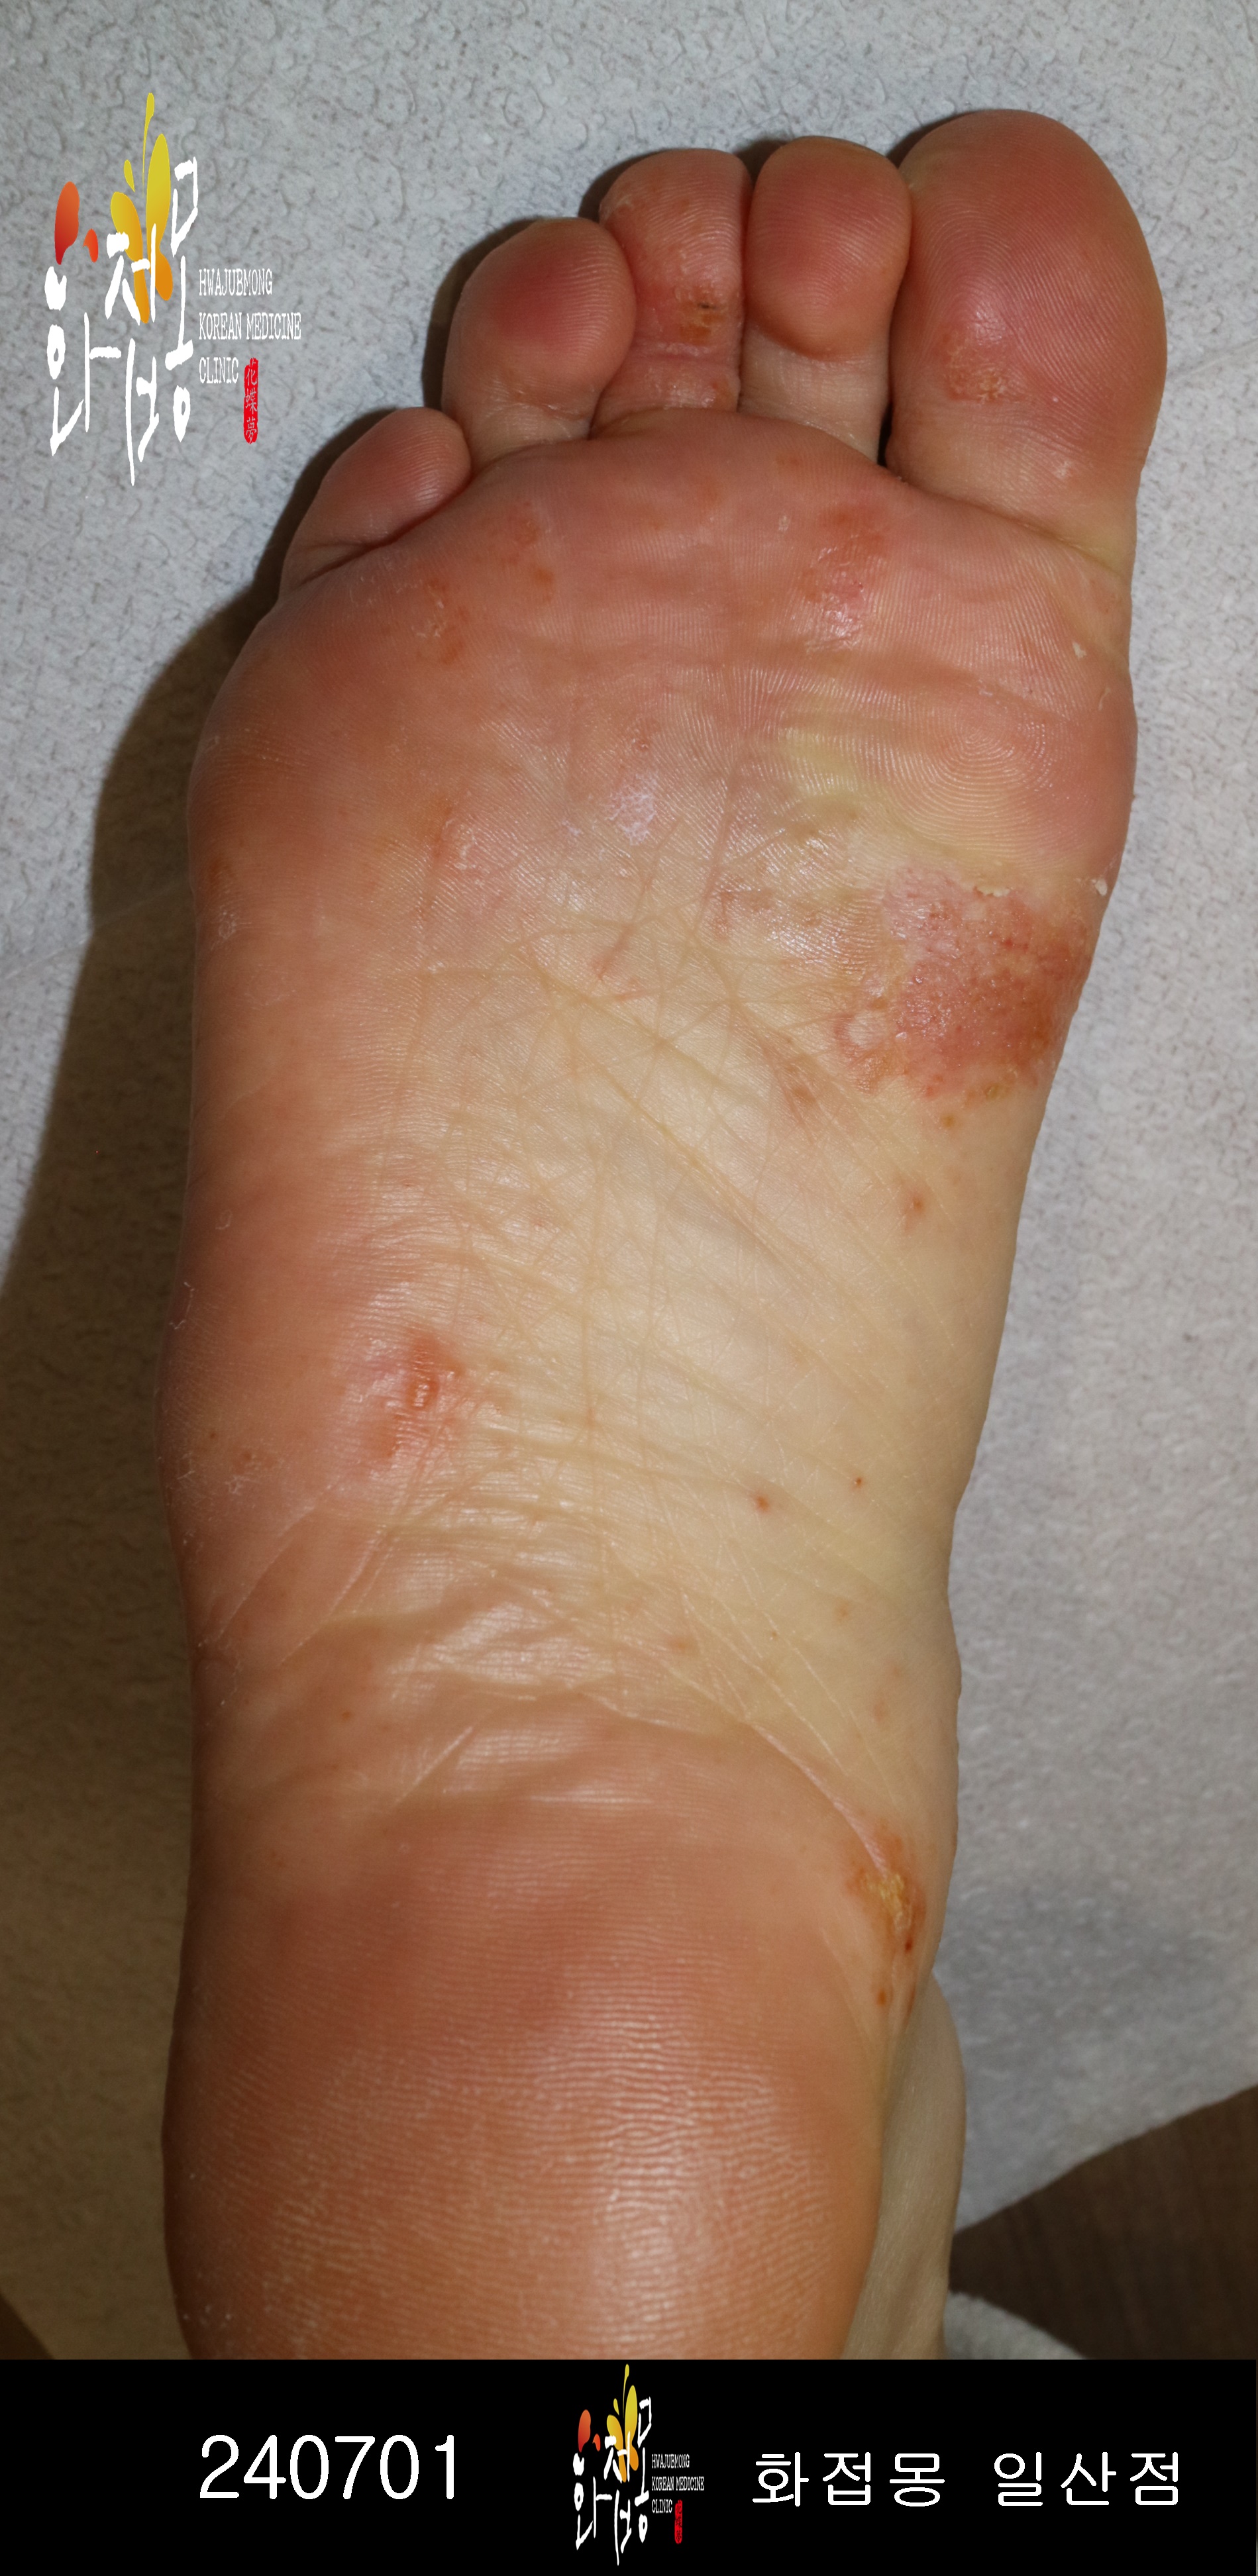

• 한포진(발)

• 치료기간

3개월

• 전) 2024-07-01

후) 2024-10-04